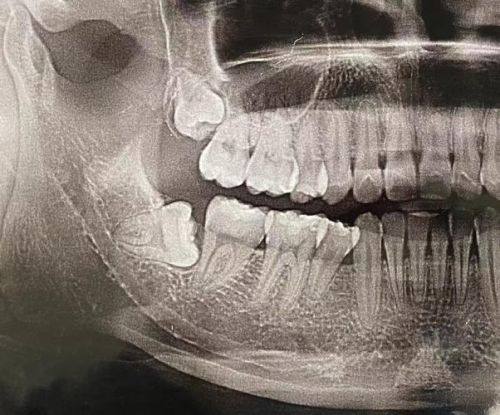

智齿拔除后留下牙洞是正常现象,大家不用过于紧张。创面愈合需要一定时间,一般来说,牙洞会在1 - 3个月逐渐被新生组织填平。在这个过程中,身体会启动自我修复机制,血会在牙洞处形成血凝块,这是愈合的第一步。血凝块就像一个“保护罩”,能防止细菌感染,为后续的组织生长提供基础。随着时间推移,血凝块会逐渐被新生的肉芽组织替代,然后慢慢形成新的牙龈组织和牙槽骨,更终让牙洞消失。